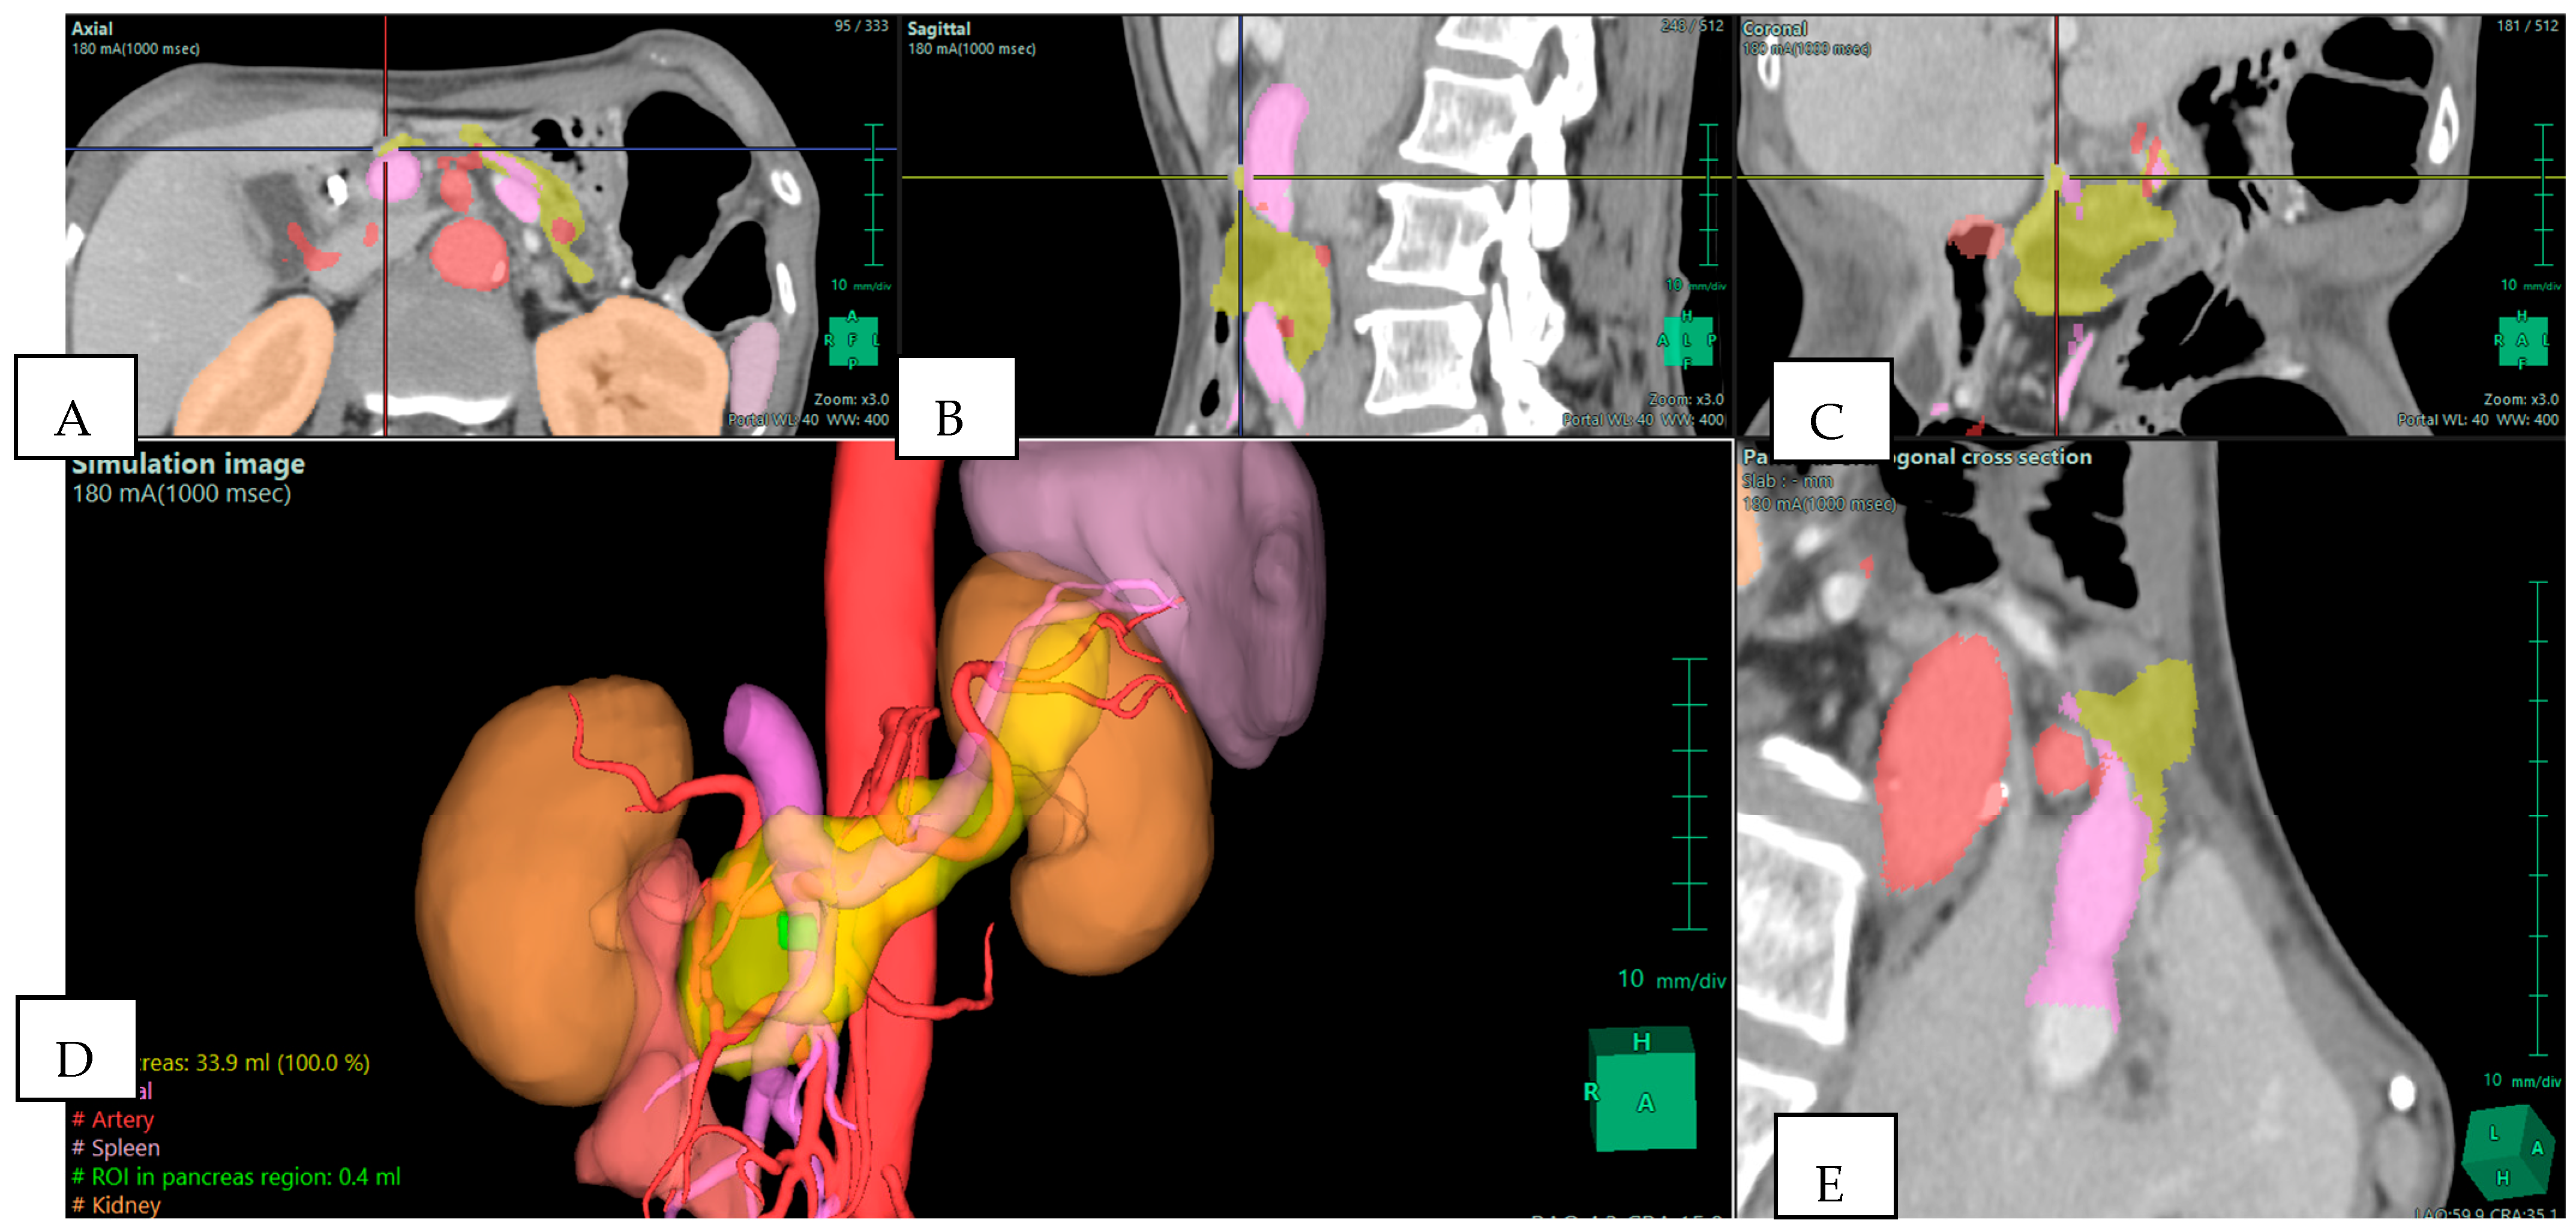

The strongest argument for integrating 3D reconstruction into preoperative planning is its demonstrated ability to alter surgical strategy. Several clinical series have reported changes in operative planning in 20–30% of cases once 3D reconstructions were reviewed. These changes typically involve revised judgments about vascular invasion, resectability, and the extent of resection required. For example, in a study of pancreatoduodenectomies, surgical plans were modified in more than one-fifth of patients after 3D evaluation, with the most frequent adjustments relating to anticipated venous resection or reconstruction [2]. In borderline resectable pancreatic ductal adenocarcinoma (BR-PDAC), where accurate assessment of venous and arterial involvement determines operability, 3D reconstructions have proven particularly useful [6,11]. They allow surgeons to visualize tumor abutment of the SMV–portal vein confluence or encasement of arterial branches in a way that 2D slices cannot, as shown in Figure 1. This not only aids in selecting candidates for upfront surgery versus neoadjuvant therapy but also prepares the surgical team for complex vascular procedures if required.

Figure 1. Preoperative Planning of a Pancreatic Head Adenocarcinoma with Main Duct Intraductal Papillary Mucinous Neoplasm (IPMN) in a 70-year-old Woman. Multiphase CT scan with 3D volume rendering shows the tumor (green) abutting the superior mesenteric vein (SMV)/portal vein (PV) confluence (purple). Images derived from anonymized clinical datasets from our institution. (A) Axial plane; (B) sagittal plane; (C) coronal plane; (D) 3D reconstruction—simulation image; and (E) pancreas orthogonal cross section. Images derived from anonymized clinical datasets from our institution.